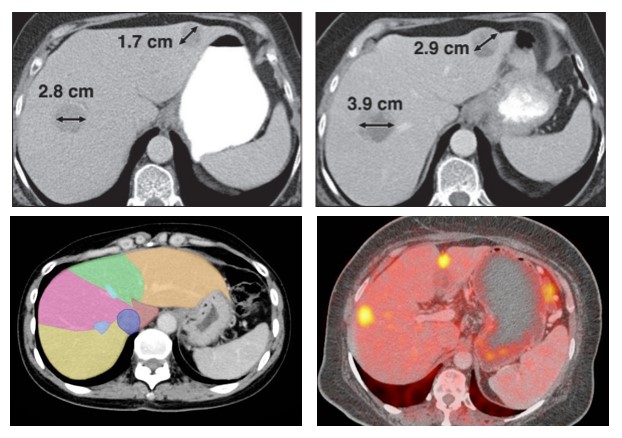

RECIST 1.1 / iRECIST

Response Evaluation Criteria in Solid Tumors provides standardized criteria for measuring the size of tumors and determining their response to therapies in clinical trials.